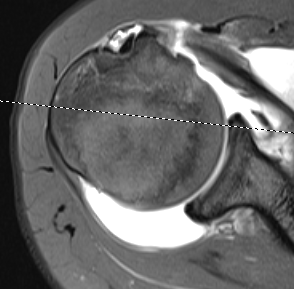

MRI

Patterns

- full thickness minimally retracted tears

- full thickness retracted tears (comma sign)

Perched long head of biceps with tear of upper border of subscapularis

Full thickness minimally retracted subscapularis tear

Full thickness retracted subscapularis tear

Full thickness retracted subscapularis tear with medial dislocation of long head of biceps tendon